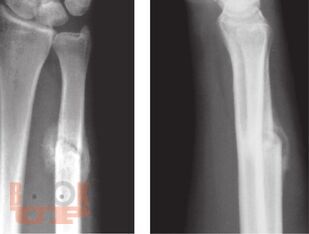

В настоящих методических рекомендациях обобщены научные данные и личный профессиональный опыт организации рентгеновской службы, описаны методы лучевой диагностики. Освещаются методы исследования органов и систем человека с нормальной анатомией, эмбриогенезом, рентгеноанатомией, а также рентгеносемиотика различных патологических состояний у взрослых и детей.